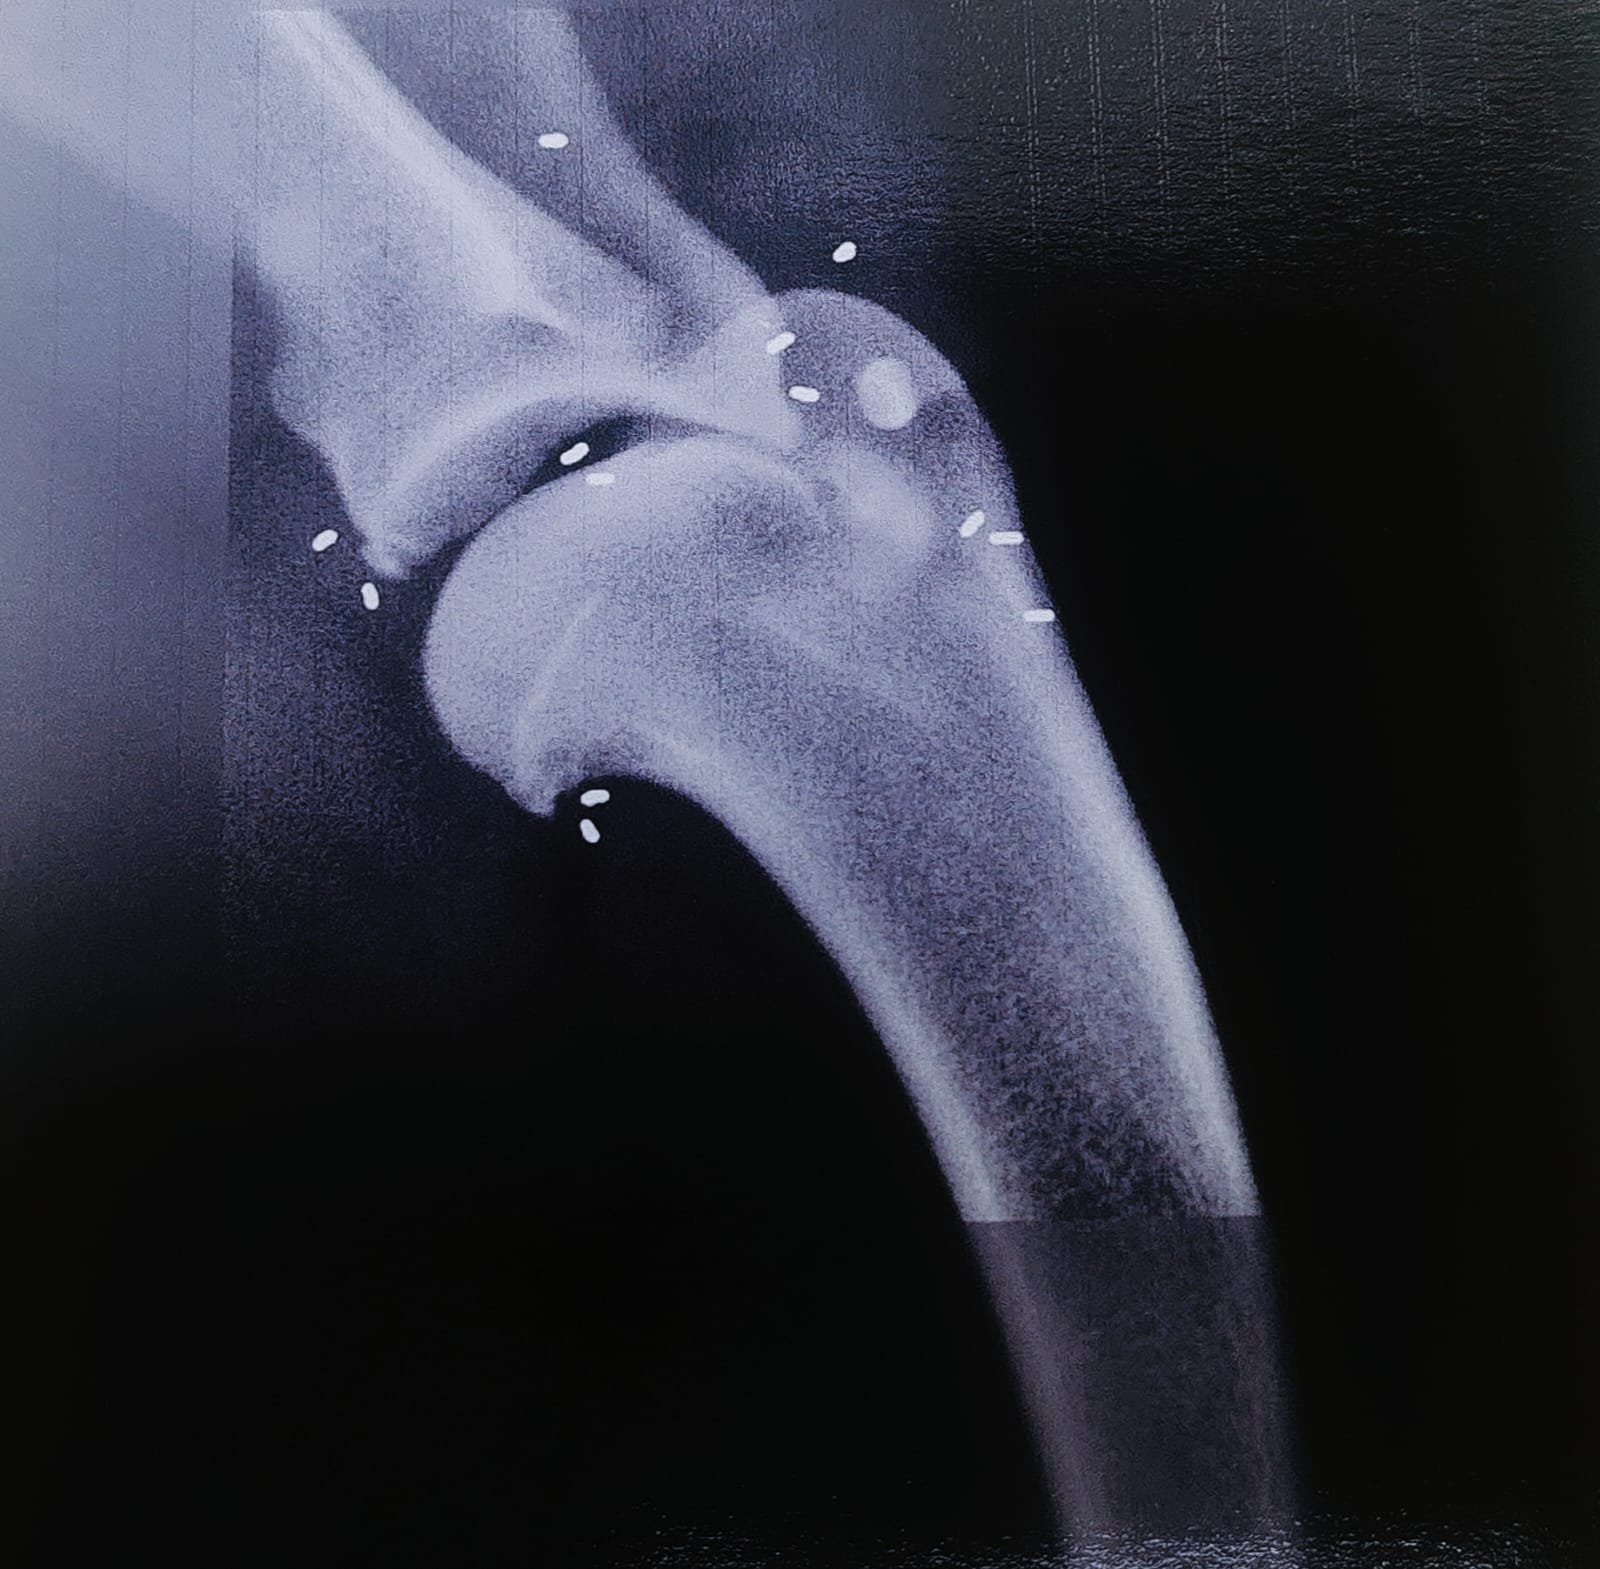

Con questa tecnica si impiantano piccoli granellini di oro (24 carati,1-3mm di lunghezza e 1mm di diametro) nel sottocute, nei muscoli, vicino a tendini e legamenti, in prossimità di articolazioni, in punti ben precisi corrispondenti a Punti di agopuntura, punti dolenti o punti corrispondenti ad alterazioni radiografiche diagnosticate. L’impianto avviene con degli aghi cavi di diametro 2,2mm in cui il granellino d’oro viene fatto cadere e perfettamente posizionato nella sede predefinita.

Radiografia spalla con presenza di grani d’ oro